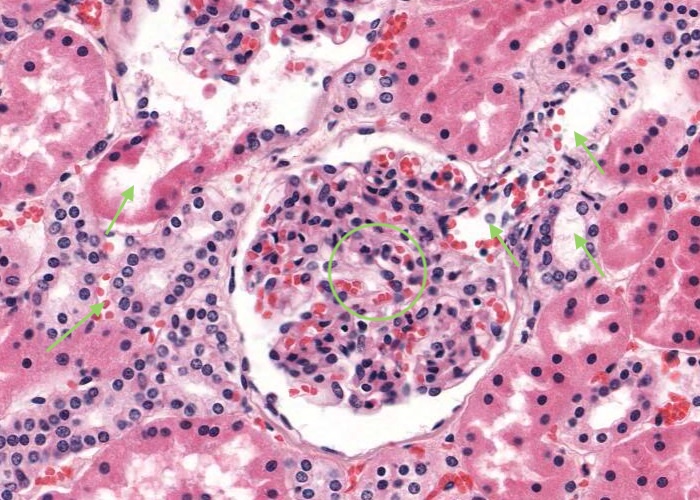

A renal corpuscle is located in the cortex and is the specialised structure where filtration occurs. Each is an aggregation of capillaries enclosed within a cup-shaped capsule called the glomerular (Bowman’s) capsule. Identify red blood cells within these capillaries. The capsule has an outer (parietal) surface layer of squamous epithelial cells and the inner (visceral) layer invests the glomerular capillaries.

The space between the glomerular capillaries and the parietal layer of Bowman’s capsule is referred to as the capsular or urinary space. This space receives plasma fluid that filters through the glomerular capillaries and the visceral layer of epithelial cells called podocytes.

In this H&E section, podocytes are difficult to distinguish from other populations of cells present (e.g. mesangial cells) but assume if you identify a cell nucleus on the periphery of the glomerulus that is larger and more spherical then it is probably a podocyte rather than a flattened nucleus belonging to an endothelial cell. You will see this distinction better when you view the renal corpscule where the basement membrane has been specifically stained and podocytes are definitely outside surface of the basement membrane of the capillary wall.

Interlobular arteries give off tiny afferent arterioles which run into the lobule to supply each renal corpuscle. An afferent arteriole enters a renal corpuscle, breaks up into a tuft of capillaries called a glomerulus, and then collects back into an efferent arteriole instead of a vein. This occurs at the "vascular pole". This is a nice image because it also shows part of a glomerulus with the urinary (tubular) pole visible (see more details in the next item). You may see an arteriole, but it will be impossible to tell whether it is afferent or efferent (although there is a slight hint that it is an afferent arteriole because it is adjacent to a distal convoluted tubule - ignore this though for now!). The efferent arteriole runs for only a short distance before breaking up into a second bed of peritubular capillaries, which nourish the proximal and distal tubules and absorb fluid. Even when these capillaries are collapsed you can easily see abundant red blood cells within their lumens between the convoluted tubules.